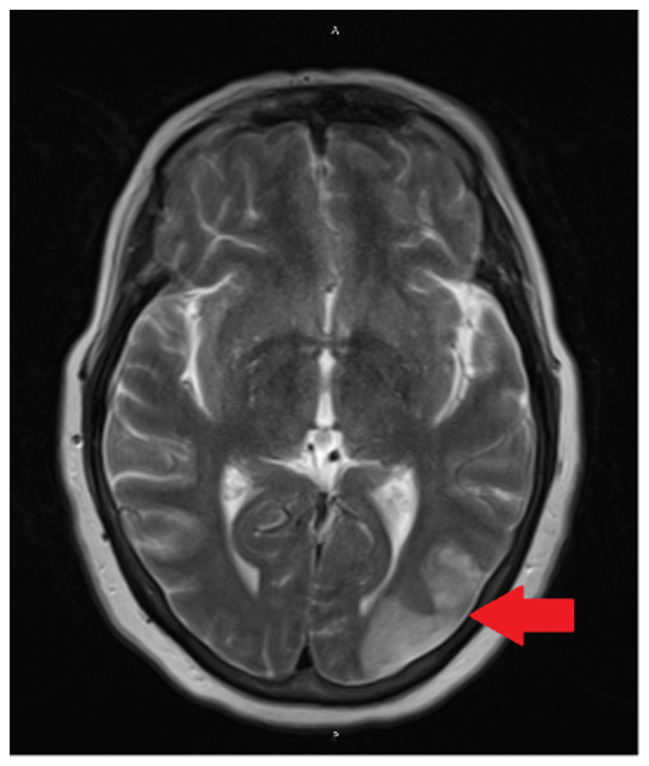

Case report: A 58-year-old woman with controlled hypertension and obstructive sleep apnea presented with recurrent unilateral pulsating headaches, nausea, and photophobia. Initially diagnosed as migraine, she later developed right homonymous hemianopia. Imaging revealed bilateral occipital and parietal strokes with intracranial vasoconstriction. Cerebral angiography confirmed vasospasm, responsive to intra-arterial milrinone. Diagnosed with reversible cerebral vasoconstriction syndrome, she was treated with nimodipine, resulting in complete symptom resolution.